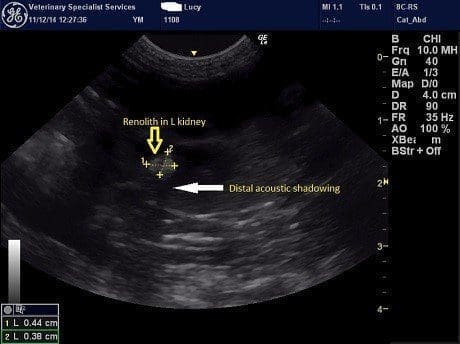

Following sedation, an abdominal ultrasound was performed focussed on the urinary tract. Both kidneys contained echogenic regions with distal shadowing consistent with renoliths (Figure 1). There was no evidence of hydronephrosis or hydroureter but both kidneys did show decreased cortical blood flow and increased cortical echogenicity. The urinary bladder revealed a focal change cranially which may reflect a scar from the site of the previous cystotomy. There was no evidence of bladder stones.

Figure 1. Ultrasound images of the left kidney (left) and right kidney (right). In both kidneys there is mineralised material (yellow arrows) with distal acoustic shadowing (white arrow).